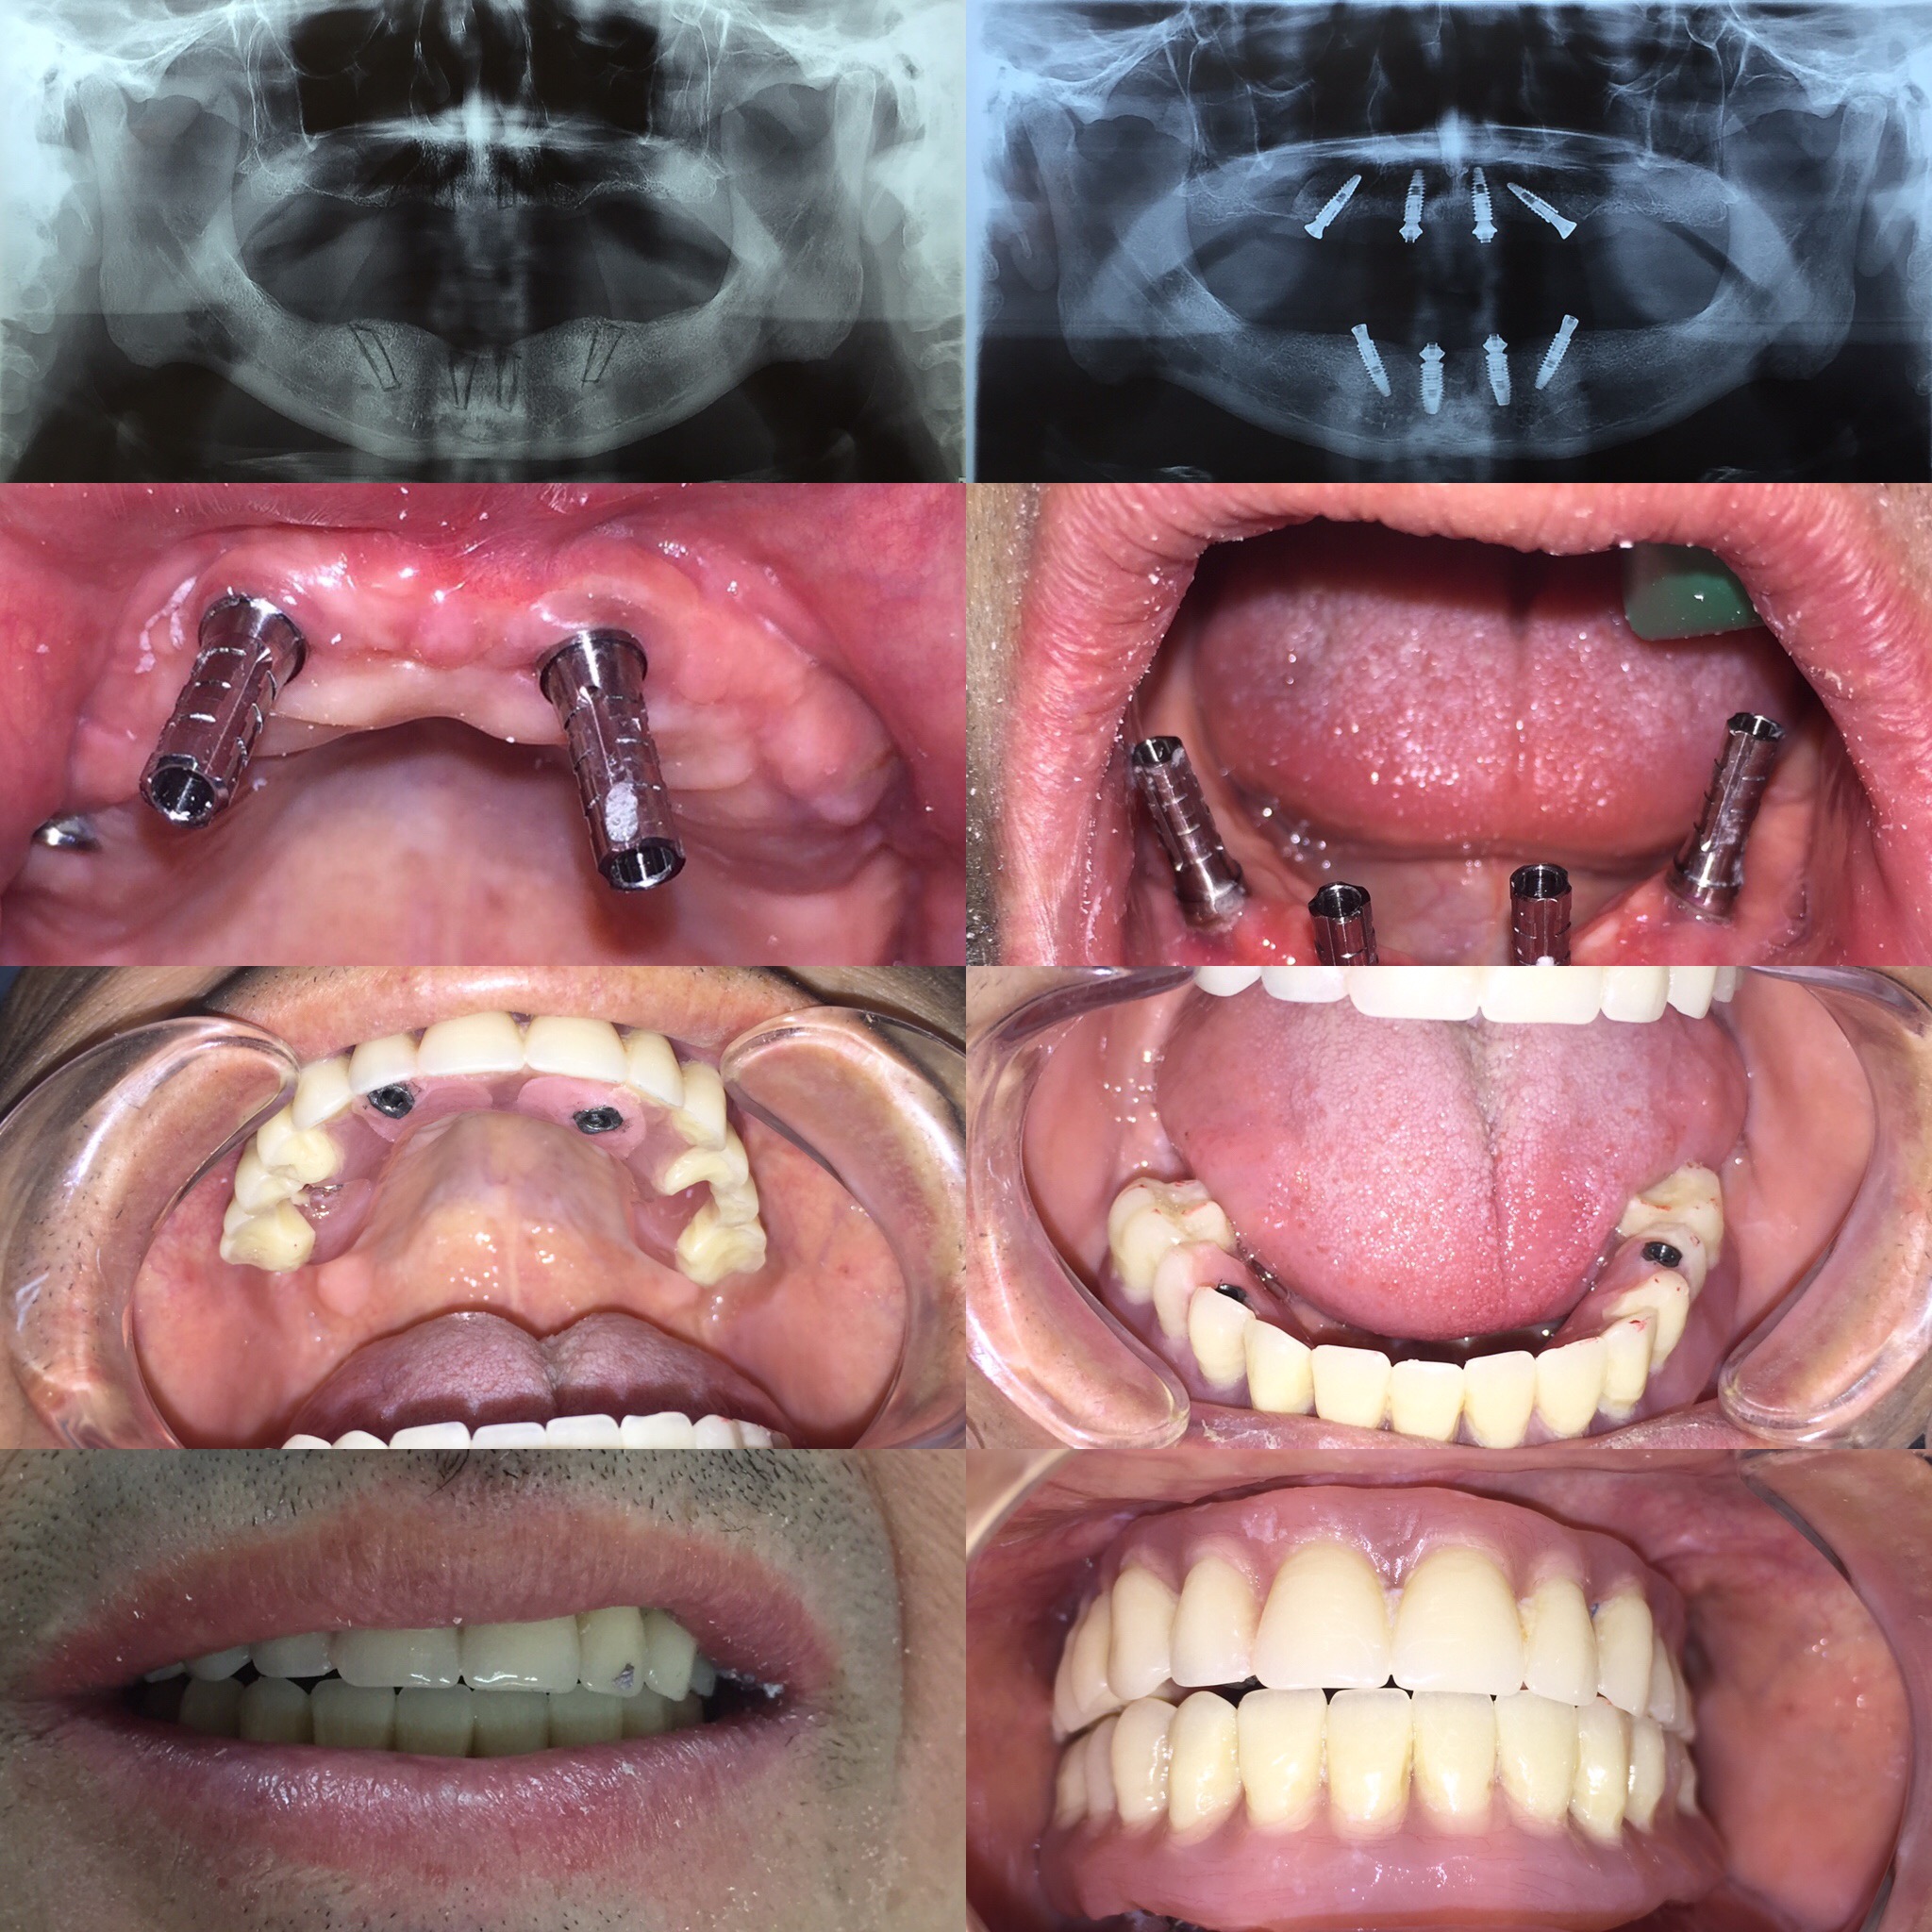

Los implantes dentales, el injerto de hueso y la rehabilitación fija son procedimientos dentales que se relacionan entre sí: El injerto de hueso es necesario para colocar implantes dentales cuando el hueso dental no tiene el volumen suficiente. De esta forma, el paciente evita tener que usar prótesis removibles.